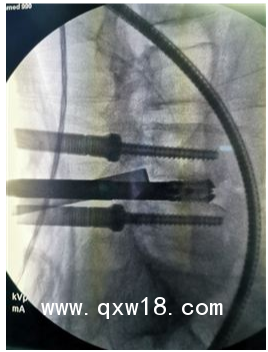

產(chǎn)品名:UBE 進(jìn)口雙通道手術(shù)醫(yī)療器械

企業(yè)名:山東奧蘇本醫(yī)療設(shè)備有限公司